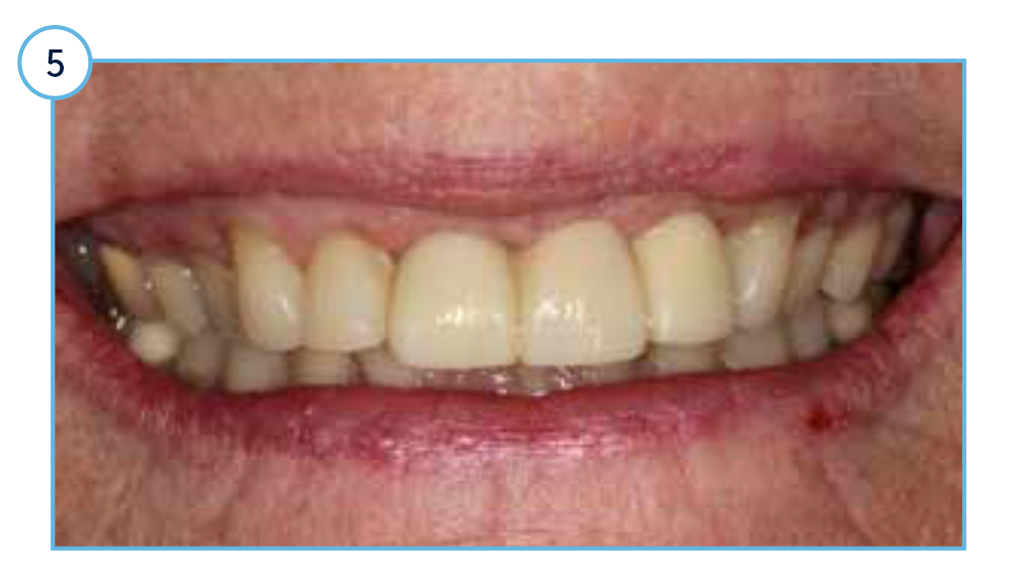

Clinical view of the aesthetic outcome one-year post restoration.